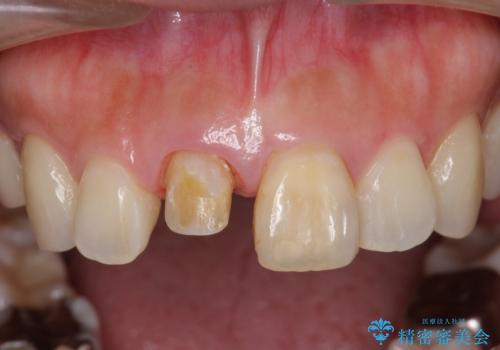

再度根管治療を行ったのちの、オールセラミッククラン治療を計画します。

天然歯を再現したリアルな仕上がりに満足いただくことができました。

オールセラミッククラウン スペシャルプランは細やかな色調の再現に優れ、目立つ前歯の審美的な仕上がりがより達成されやすいプランです。